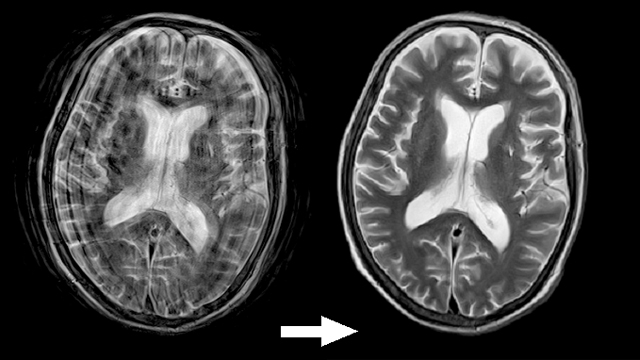

原理的に磁場が強いほど高画質な画像が得られますが、3T-MRIは臨床で用いられているものの中でも最も磁場の力が強く、今まで見つけにくかった病変も明瞭かつ詳細に描出できるようになりました。

画質向上だけでなく検査時間短縮も可能となりました。特に腹部などの息止めが必要な検査において、従来20秒前後かかっていた範囲も8秒ほどで撮影できるようになり、年配の方などにも優しいものとなっています。

モーションアーチファクト